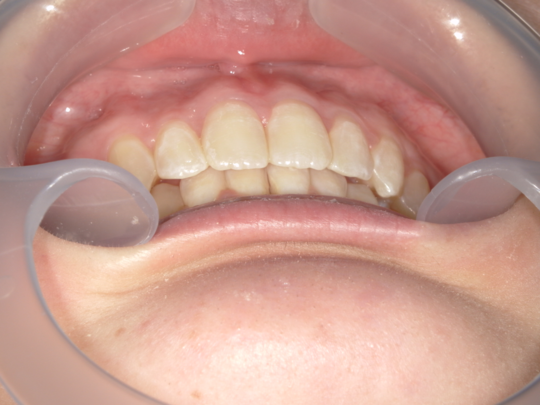

治療後

治療の副作用(リスク)歯の動き方には個人差があり、予想された治療期間が延長する可能性があります。。マウスピースの使用状況、矯正歯科治療には患者さんの協力が必要であり、それらが治療結果や治療期間に影響します